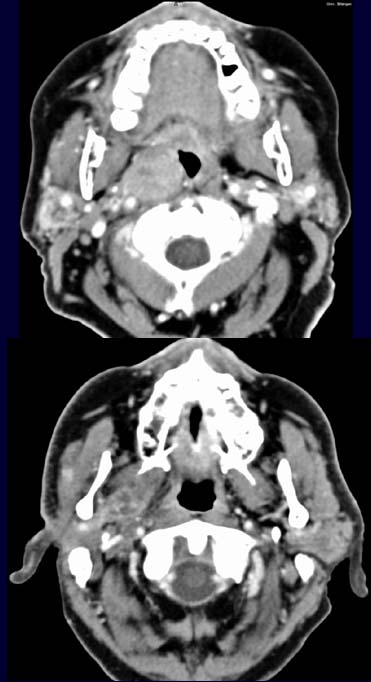

Im

CT-Schnitt durch die Mundhöhle nach Kontrastmittelgabe (oberes Bild)

kommt die rechte Tonsille vergrößert

und kontrastmittelaufnehmend zur Darstellung. In einem axialen Schnitt

weiter cranial kommt der M. pterygoideus rechts inhomogen

kontrastmittelaufnehmend und vergrößert zur Darstellung.